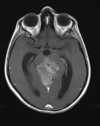

A

Cisto epidermóide

Hipersinal na difusão

Sinal heterogêneo no FLAIR

Extra-axial